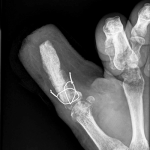

NOTA TÉCNICA

586

“Técnica del reciclado” para la reconstrucción en un tiempo de una mano metacarpiana

Pablo E. Valle, Lucas F. Loza, Nicolás Cardinal, Alejandro Fazio, Fernando J. Cervigni